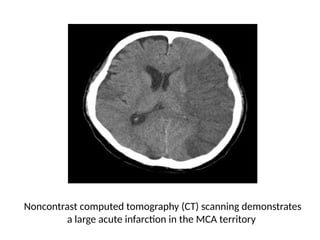

Noncontrast computed tomography (CT) scanning demonstrates

a large acute infarction in the MCA territory